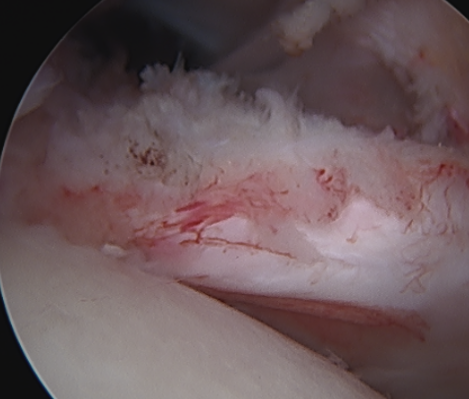

Comma sign

- medially retracted subscapularis tear

- exposes the superior insertion of superior glenohumeral ligament / coracohumeral ligament

Full thickness retracted subscapularis tear with comma sign